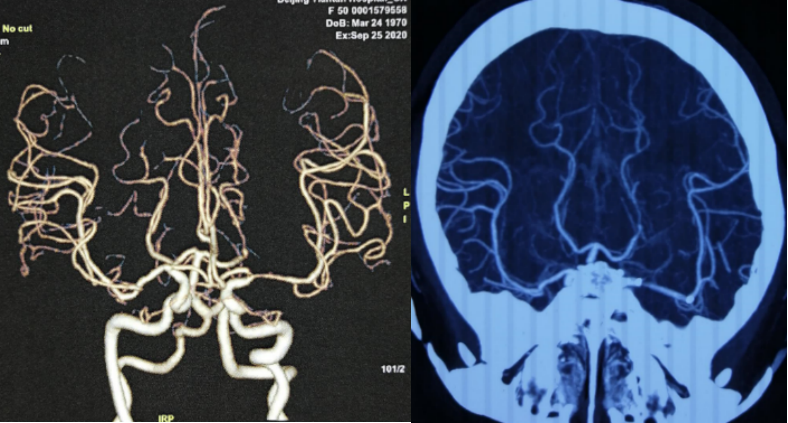

脑血管检查2021.02.20天坛医院:左侧大脑中动脉支架置入术后,局部管腔纤细,远端分支减少,左侧大脑后动脉P2局限性狭窄,左侧颞顶叶可见斑片状TTP,MTT延长,CBF略低。

术后4个月复查,CTA示支架近端可疑再狭窄 (2020.09,天坛医院)

术后9个月再次复查CTA示左侧大脑中动脉支架内重度狭窄 (2021.02.18天坛医院)